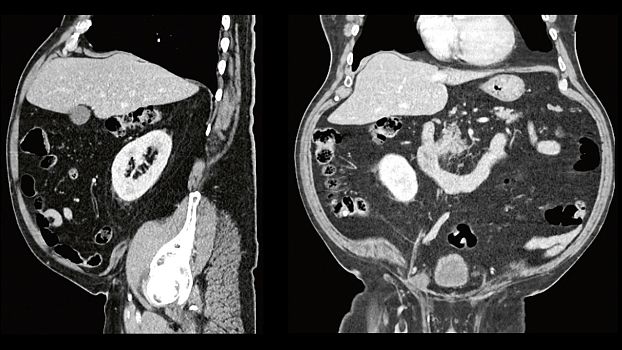

Клинические изображения

SOMATOM go.Up - компьютерный томограф для проведения рутинных и целевых осмотров, лучевой терапии и ангиографии. Система отличается инновационным дизайном рабочего места и полностью обновлённой концепцией сервиса, которая способствует снижению расходов по эксплуатации. Подходит для обследования головного мозга, легких, толстой кишки, сердца, сосудов. Вы можете заказать или купить со склада в наличии компьютерный томограф Siemens SOMATOM go.Up по выгодной цене, от надежного официального дистрибьютора "МСТ", с бесплатной доставкой в любой город по всей России.

SOMATOM go.Up позволяет расширять клинический диапазон и развиваться, достигая существенных результатов. Благодаря использованию высоких технологий система обеспечивает результаты, которые ранее были доступны только на томографах высокого класса. Кроме того, SOMATOM go.Up хорошо подходит для целей лучевой терапии. Благодаря пакету RT Image Suite, установленном на рабочей станции сбора данных, можно без труда выполнять разметку, оценивать изображения и проводить оконтуривание мишеней для лучевой терапии.

SOMATOM go.Up позволяет проводить высококачественные ангиографические исследования сосудов с хорошим контрастным усилением, субмиллиметровыми срезами и точной синхронизацией по времени.

SOMATOM go.Up позволяет проводить скрининговые исследования лёгких и толстой кишки, а также исследования сердца для оценки коронарного кальция. Благодаря субмиллиметровой коллимации SOMATOM go.Up обеспечивает высокое пространственное разрешение, тем самым повышая чувствительность диагностики в онкологии.